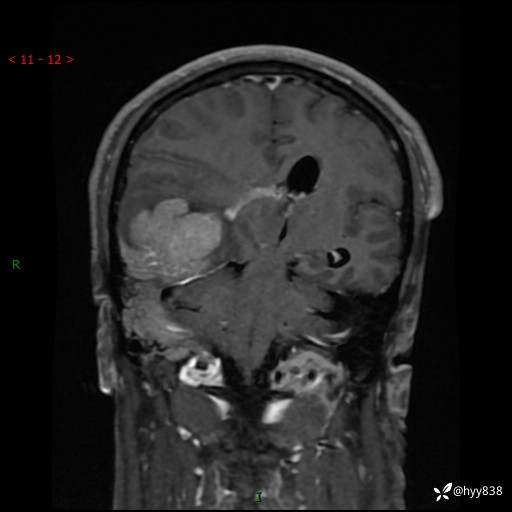

患者性别:男

患者年龄:56岁

简要病史:外院CT提示脑膜瘤,为进一步诊治来我院

临床诊断:颅脑占位

颅脑MRI平扫+增强